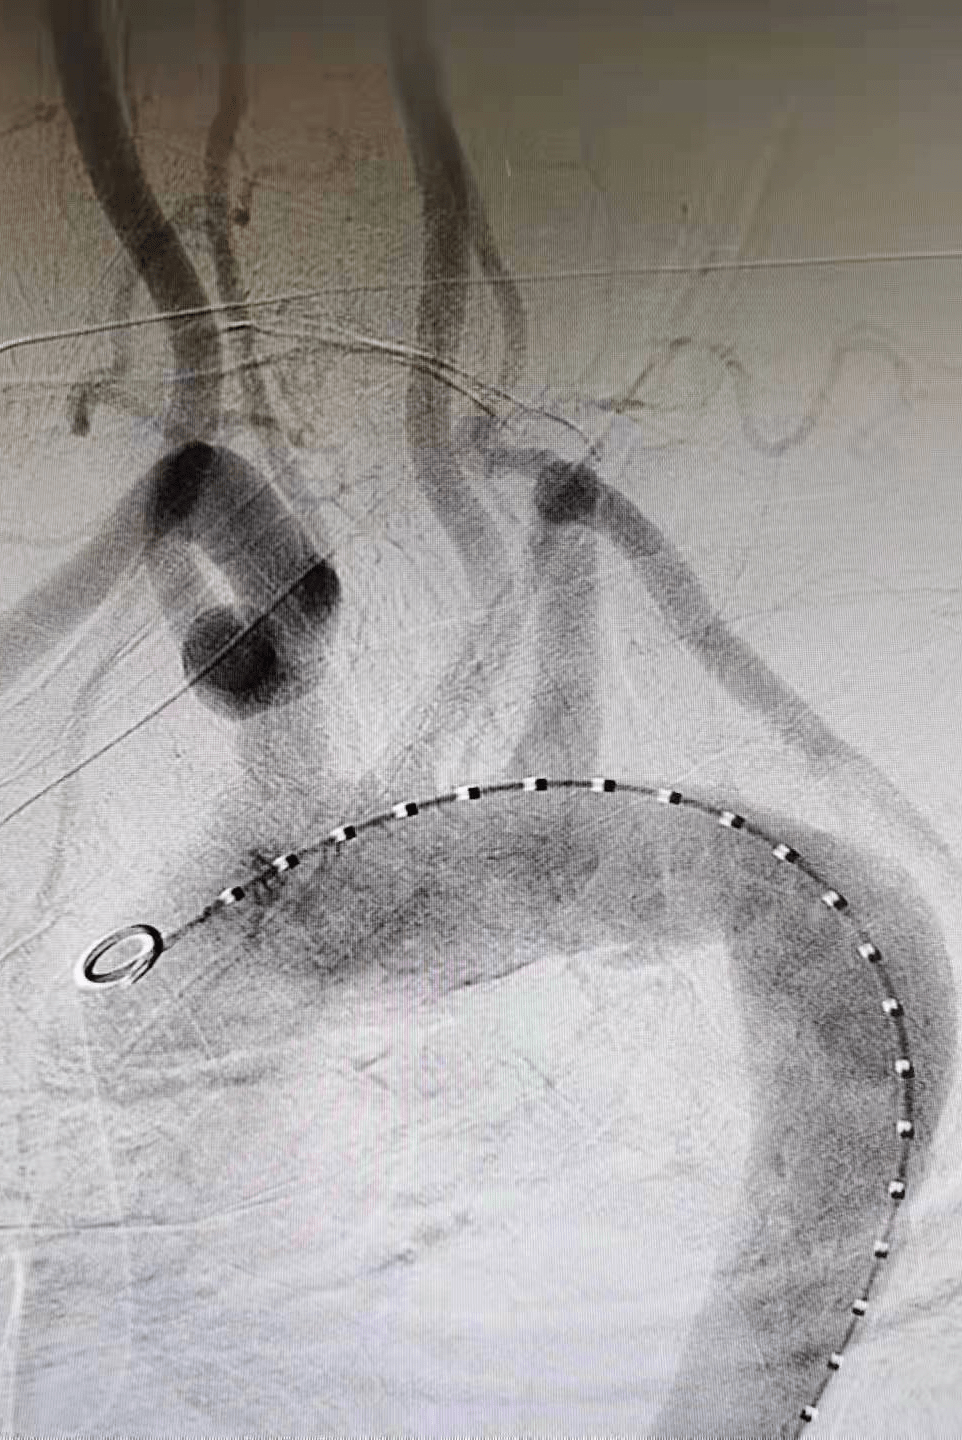

在介入手术室王素娟护士长和付晓慧、陈浩等护士积极配合下 , 刘洪主任带领潘仲杰和郑鹏远两位医生 , 沿患者右侧股总动脉造影(见图二、图三)置入胸主动脉覆膜支架 , 于左颈总动脉的左侧缘 , 先覆盖左侧锁骨下动脉 , 再经左肱动脉进行穿刺 , 用可调弯鞘在左锁骨下动脉开口处体内原位开窗(见图四) , 经球囊扩张窗口(见图五) , 置入球扩覆膜支架(见图六) , 保证了患者主动脉及左锁骨下动脉血流 。

(图二)